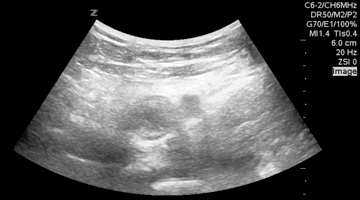

QA of the Day. Know where to measure GB wall thickness #foamus #foamed #meded #pocus